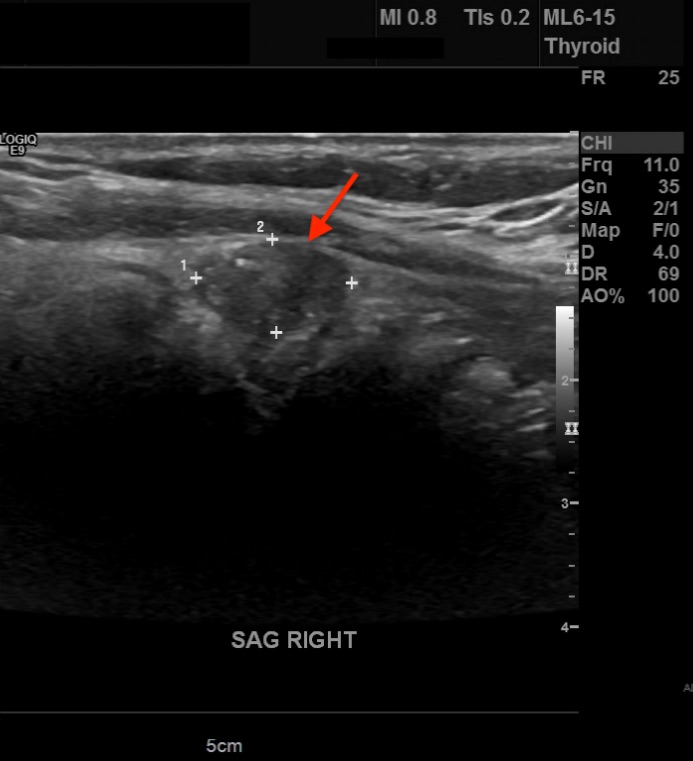

Diagnostic tests. His thyrotropin level was normal (0.495 mIU/L; reference range, 0.49-4.67 mIU/L). Findings of initial neck US performed at an outside hospital identified a solitary right thyroid nodule. Repeated US revealed 3 nodules that were greater than 1 cm in diameter and a few subcentimeter-sized nodules. In the central aspect of the right lobe was an ill-defined, 3.1-cm, heterogeneous, isoechoic solid nodule with mildly irregular margins, microcalcifications, a taller-than-wide shape, and increased vascularity (Figure 1). In the left aspect of the isthmus was a well-circumscribed, 1.3-cm, ovoid solid nodule with internal microcalcifications, a wider-than-tall shape, and peripheral vascularity (Figure 2).

Figure 1. A 3.1-cm, ill-defined, heterogeneous, isoechoic solid nodule (arrow) with irregular margins, microcalcifications, and a taller-than-wide shape in the right lobe of the thyroid.